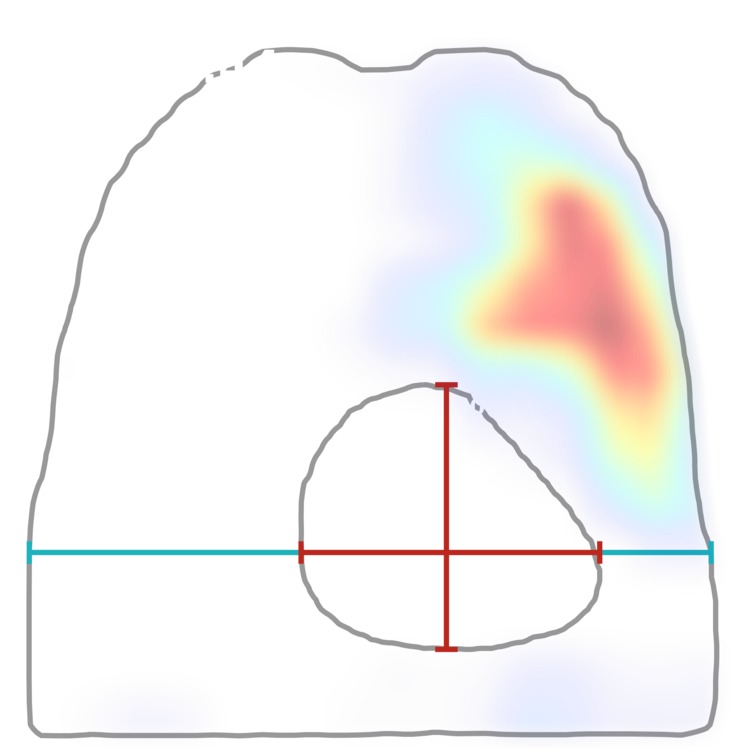

ИИ и умные алгоритмы для анализа рентгеновских снимков черепа. Обнаружение синусита и процента заполненности пазух носа менее чем за 30 секунд